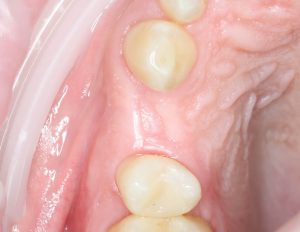

Всё. Операция закончена:

Теперь делаем контрольные снимки и оцениваем результаты собственной работы.

Послеоперационный период.

Как правило, послеоперационный период сопровождается рядом симптомов, главными из которых являются кровотечение и припухлость в области операции. К примеру, вот тот же пациент через два дня после операции:

Он полностью трудоспособен и не испытывает никакого дискомфорта. Отёков, как видите, тоже нет. Но было кровотечение. И это видно по состоянию послеоперационной раны:

На формирователе и швах повис большой кровяной сгусток. This is хорошо, поскольку он как защитная повязка, прикрывает рану от воздействия извне. Возможно, именно этим объясняется отсутствие каких-то неприятных симптомов в послеоперационном периоде.